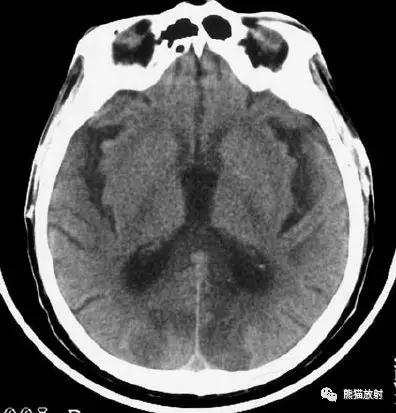

右侧大脑中动脉区域梗死的典型演变:

a)急性期

b)早期亚急性期(2天,从临床起病开始)

c)亚急性晚期(2周后)

d)慢性期(一年后)